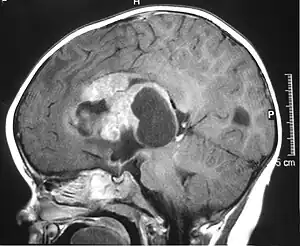

MRI of an AT/RT

The initial diagnosis of a tumor is made with a radiographic study (MRI[20] or CT-). If CT was performed first, an MRI is usually performed as the images are often more detailed and may reveal previously undetected metastatic tumors in other locations of the brain. In addition, an MRI of the spine is usually performed. The AT/RT tumor often spreads to the spine. AT/RT is difficult to diagnose only from radiographic study; usually, a pathologist must perform a cytological or genetic analysis.

AT/RTs can occur at any sites within the CNS; however, about 60% are located in the posterior fossa or cerebellar area. The ASCO study showed 52% posterior fossa; 39% sPNET; 5% pineal; 2% spinal, and 2% multifocal.[1]

The tumors' appearance on CT and MRI are not specific, tending towards large size, calcifications, necrosis (tissue death), and hemorrhage (bleeding). Radiological studies alone cannot identify AT/RT; a pathologist almost always has to evaluate a brain tissue sample.

The increased cellularity of the tumor may make the appearance on an uncontrasted CT to have increased attenuation. Solid parts of the tumor often enhance with contrast MRI finding on T1 and T2 weighted images are variable. Precontrast T2 weighted images may show an isosignal or slightly hypersignal. Solid components of the tumor may enhance with contrast, but not always. MRI studies appear to be more able to pick up metastatic foci in other intracranial locations, as well as intraspinal locations.

Preoperative and follow-up studies are needed to detect metastatic disease.